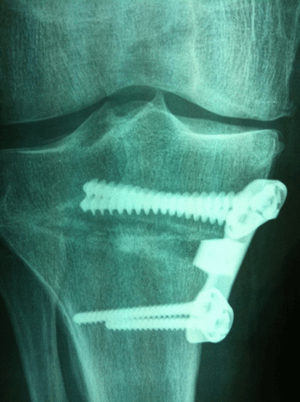

- Une cale métallique, en général incorporée dans la plaque vissée qui permet de fixer la fracture (Voir radio ci-contre).

Pour maintenir l'écartement obtenu, on peut utiliser une cale métallique d'une épaisseur choisie (8mm par exemple) pour obtenir la correction d'axe voulue (environ 8°).

La cale peut être intégrée dans le matériel de fixation comme sur la radio ci-contre.